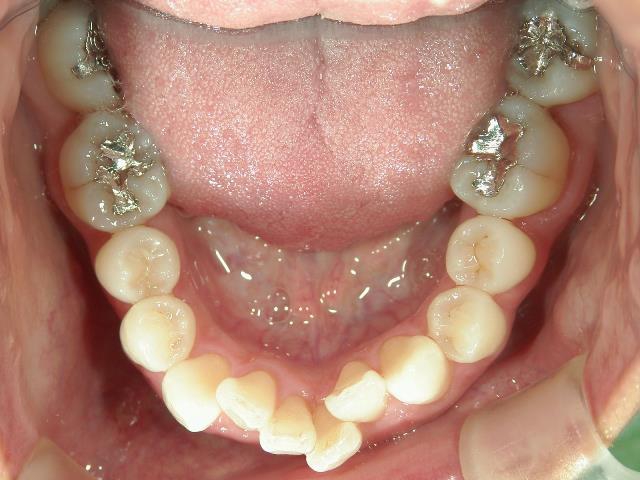

主訴:下の前歯の歯並びが乱れていて、舌に当たって痛い。

矯正_灰色.pngno.41_8994_治療前_下.JPG矯正_灰色.png